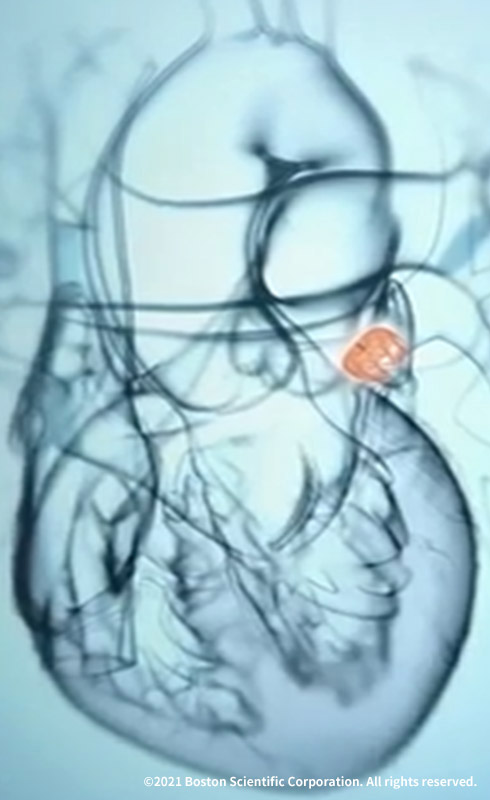

非弁膜症性心房細動の患者さんでは、脳卒中の原因となる血栓の90%以上が左心房に起始する左心耳(LAA:Left Atrial Appendage)で形成されたものです。

WATCHMANはこのLAAを閉鎖して血栓の形成を防ぎます。手技は経静脈的心房中隔穿刺法であり、カテーテル室において全身麻酔下で実施します。

WATCHMANを展開し、LAAに留置します。

WATCHMANを覆うように内皮化が進み、LAAが永久的に閉鎖されます。患者さんは、手技後約45日間は抗凝固薬の内服を継続します。経食道心エコーで閉鎖していることを確認します。

WATCHMANの働き

左房に存在する左心耳(LAA)というポケットに血栓が形成され、これが脳やほかの臓器に流れて梗塞(塞栓)を引き起こします。

WATCHMANは心臓の左心耳(LAA)と呼ばれる部分に留置されます。

WATCHMANは時間が経つと、内皮に覆われて完全にLAAを閉鎖します。

WATCHMANは心臓内に永久留置をするデバイスで、脳卒中の原因となる血栓を形成することが多い、左心耳(LAA:Left Atrial Appendage)を直接閉鎖します。血栓形成の好発部位が消失することで、予防として内服していた抗凝固剤を中止できます。

心房細動は、心臓の上部にある2つの部屋(心房)が小刻みで不規則な拍動(細動)をする不整脈です。この疾患によって、心臓の左心耳(LAA:Left Atrial Appendage)に血液が滞留して血栓が形成されることがあります。血栓が動脈を通って脳に達すると脳卒中に至る場合があります。

- 非弁膜症性心房細動では、左心耳(LAA)と呼ばれる小さな袋で形成される血栓が脳卒中の主な原因と考えられています。